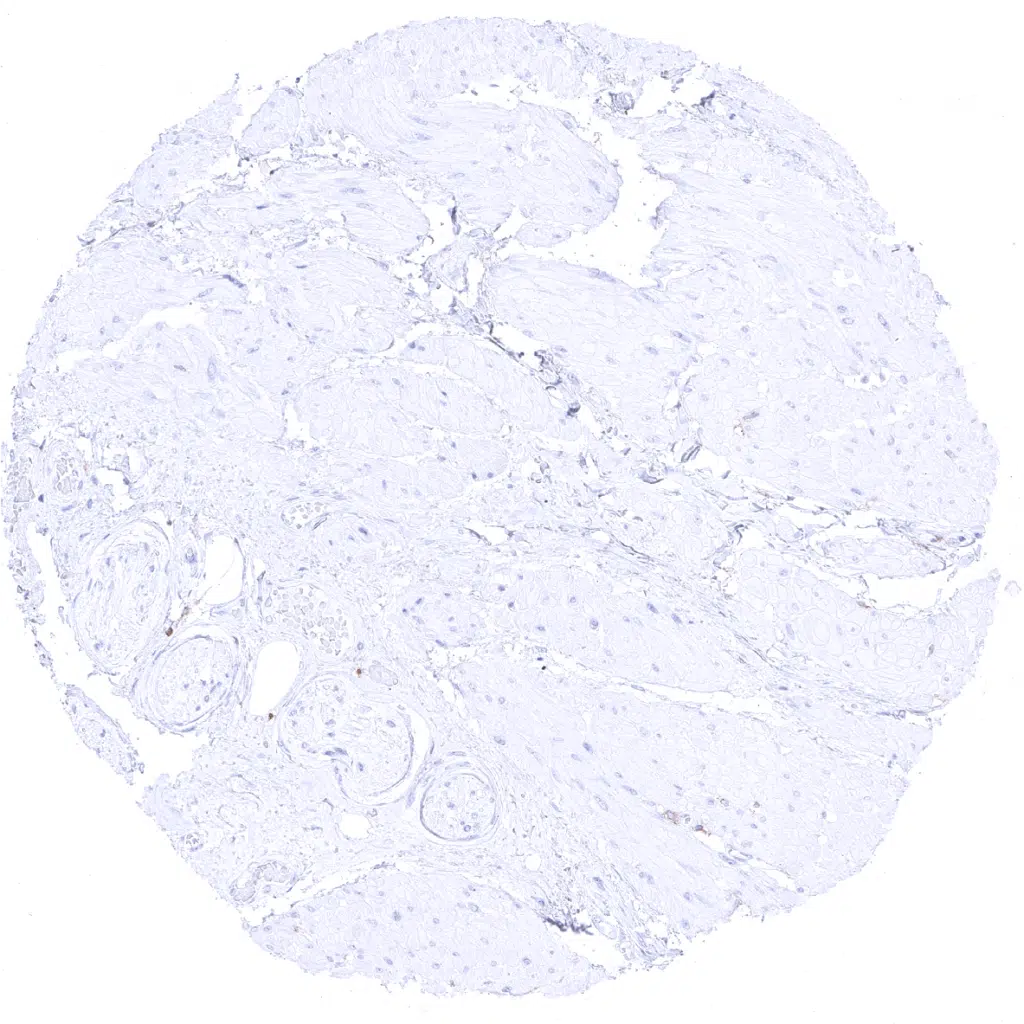

Prostate